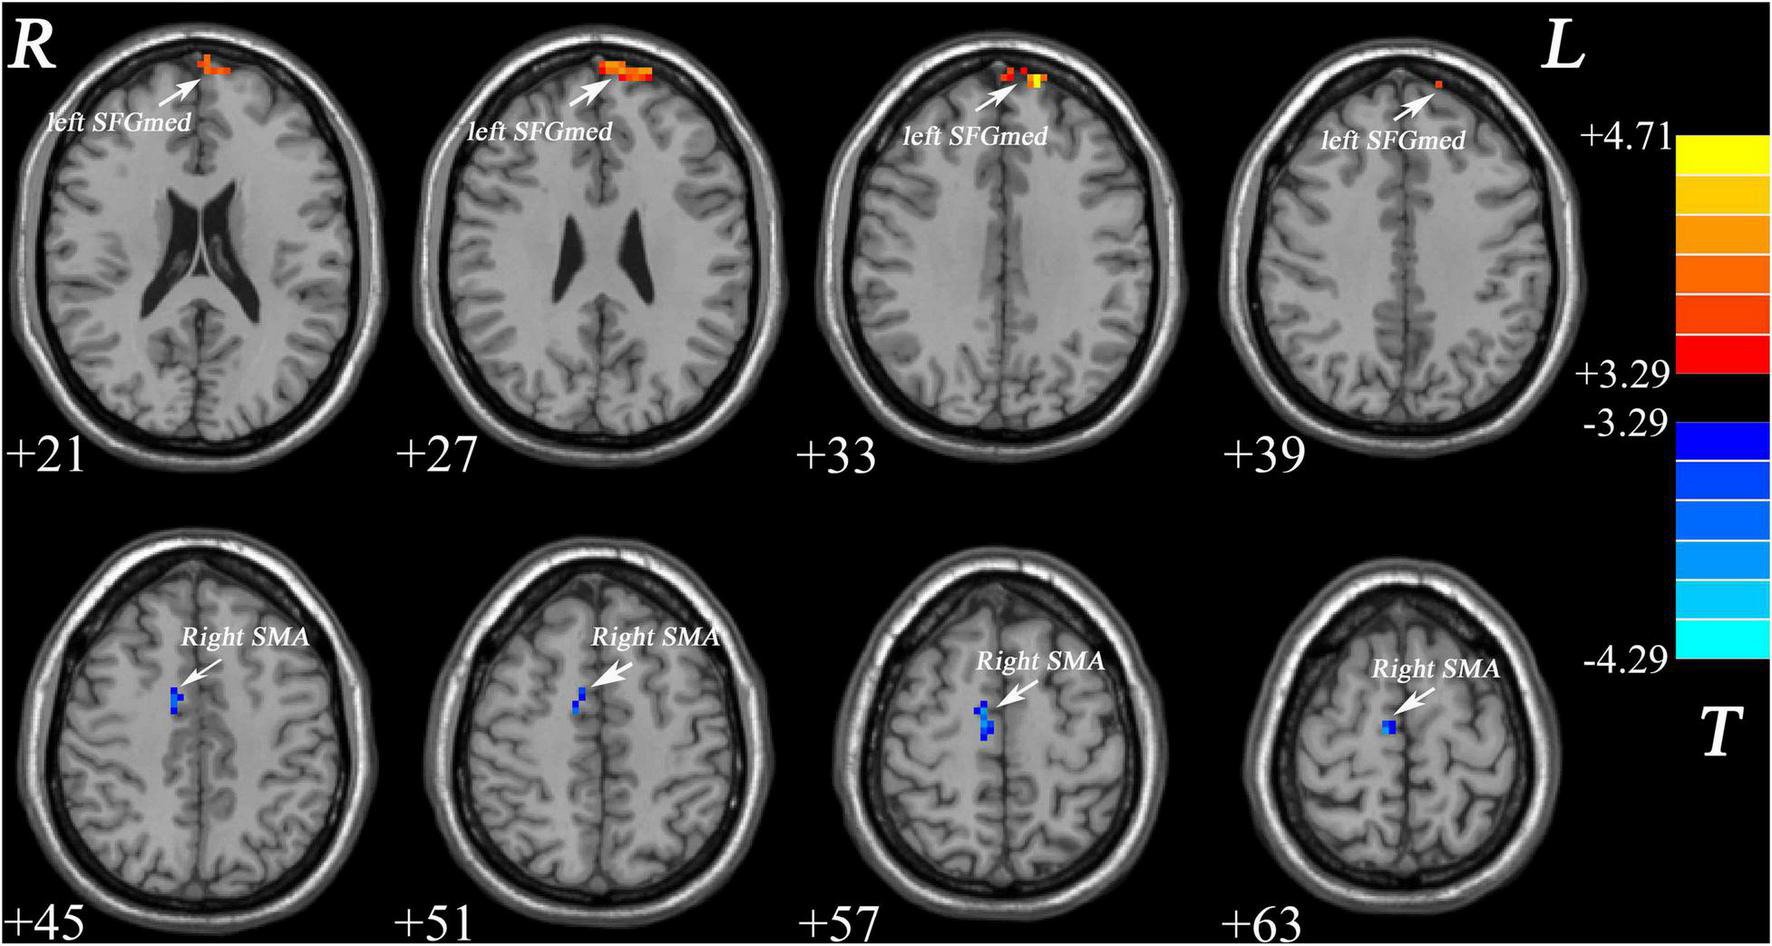

Group Differences in Global-Brain FC

As shown in Figure 1 and Table 2, patients with MDD exhibited decreased GFC values in the right supplementary motor area (SMA) (t = −4.2841, p < 0.001) and increased GFC values in the left medial superior frontal gyrus (SFGmed) (t = 4.6535, p < 0.001) compared with the control group. No other differences were observed in the patients.

Increased GFC values in the left SFGmed and decreased GFC values in the right SMA were observed in patients with MDD relative to healthy controls. GFC, global-brain functional connectivity; SFGmed, medial superior frontal gyrus; SMA, supplementary motor area; MDD, major depressive disorder.